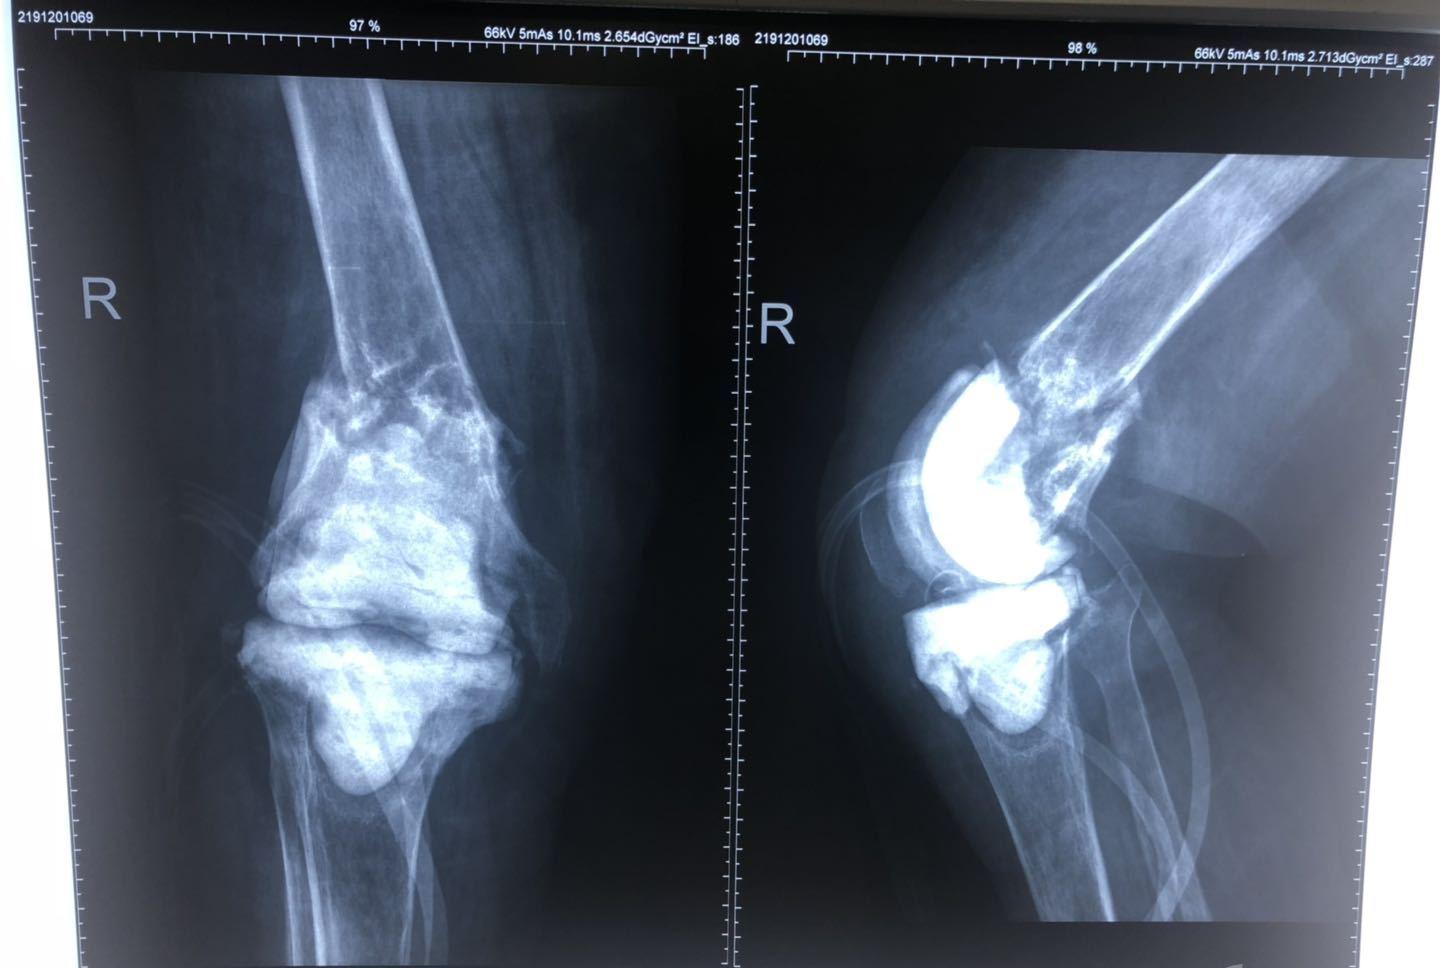

1、X线检查

X线片显示早期髌上囊肿胀,局部有骨质疏松。长期发病可出现关节间隙进行性狭窄和边缘骨侵蚀。晚期骨质破坏加重,关节间隙消失,严重时发生胫骨后半脱位。如果没有混合感染,骨质疏松就会很严重,如果混合感染,就会发生骨质硬化。